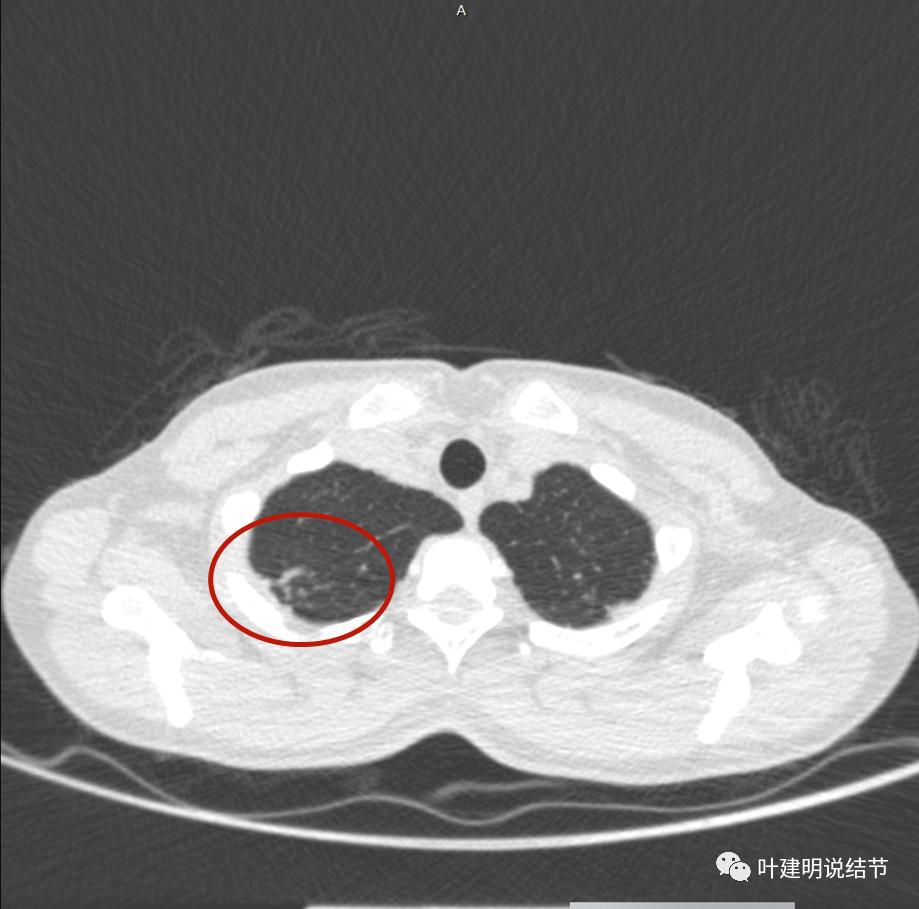

上面是她提供的病史资料,其中最重要的是PPD强阳性!其他主要看影像,我们先来看她2020年7月份的平扫片子(由于片子较多,详细展示是为了同道分析,我在影像特征描述上将只选取部分加以说明):

右肺尖偏实性结节(粉色箭头),邻近胸胸膜明显增厚不平,且广基附在胸壁上(蓝色箭头)